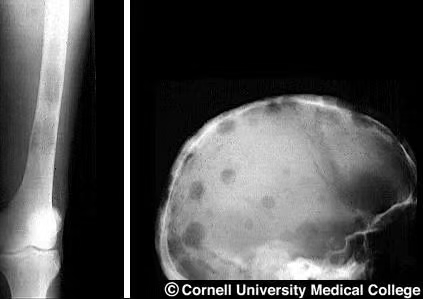

4.骨痛:癌细胞破坏骨骼,可能出现全身痛、腰背痛、四肢骨痛,活动时更明显,甚至可能发生骨折(病理性骨折)。

3.影像学检查:比如骨扫描、CT或MRI、PET/CT,能发现骨骼被破坏的部位。